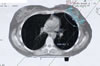

Mammakarzinom